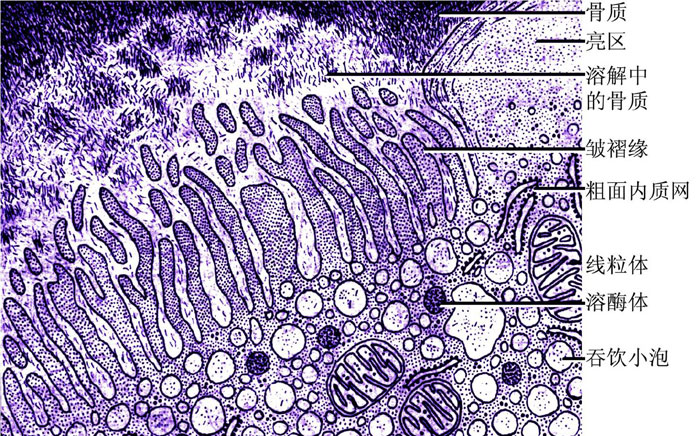

图7 成骨细胞和破骨细胞注:成骨细胞常多个成簇分布,有时单个存在,呈